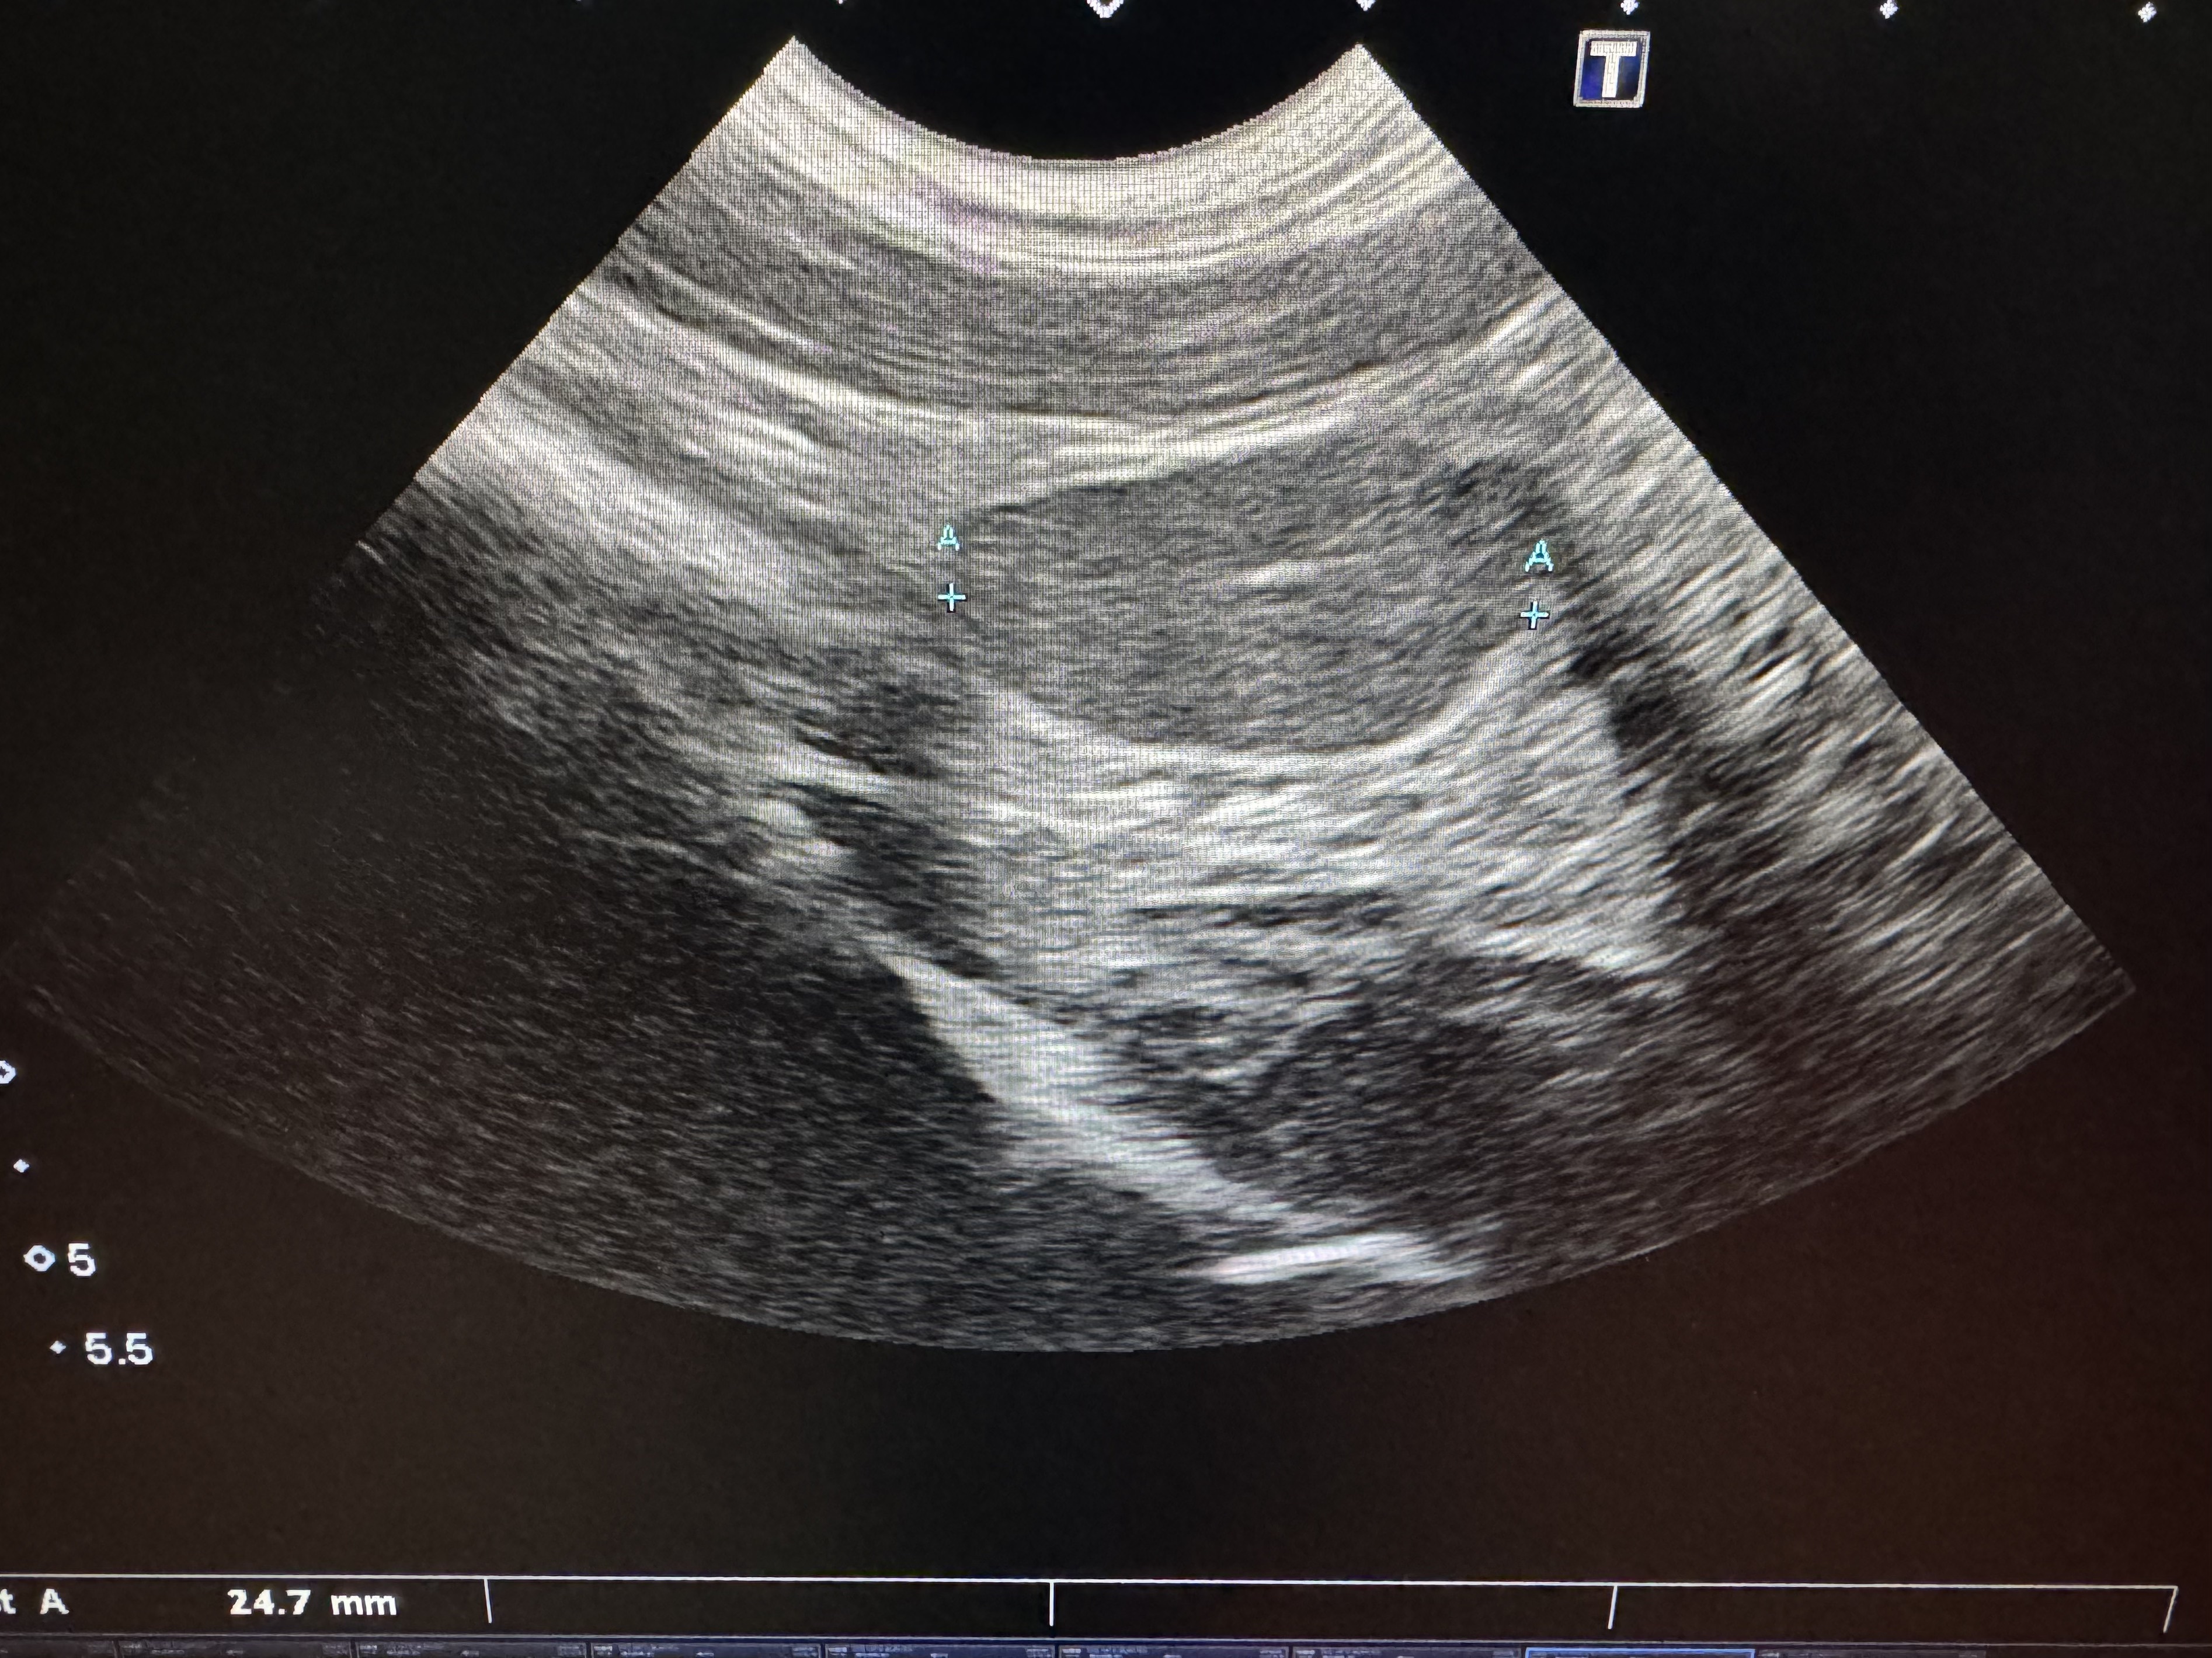

この写真は1歳のボーダーコリーの男の子の腹腔内停留精巣の腹部エコーの図です。陰嚢内に精巣が一つしか触知されず、腹部エコーによって膀胱の右鼠径間付近のお腹の中に精巣があることがわかった事例です。この子はこの後、開腹手術によって安全に去勢手術を行うことができましたので、精巣腫瘍になるリスクを事前に抑えることができました。